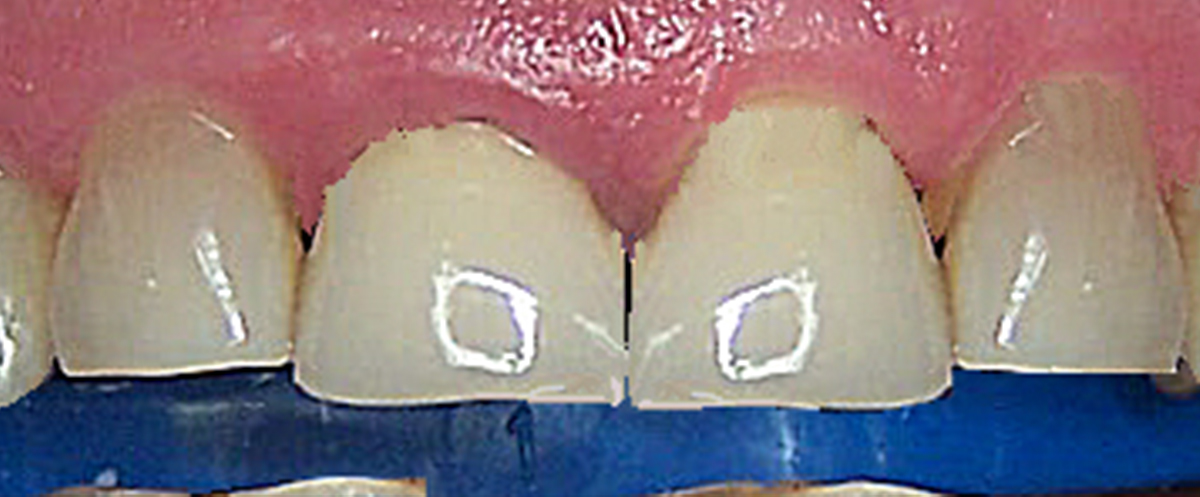

Big Centrals

-

Before

After

After